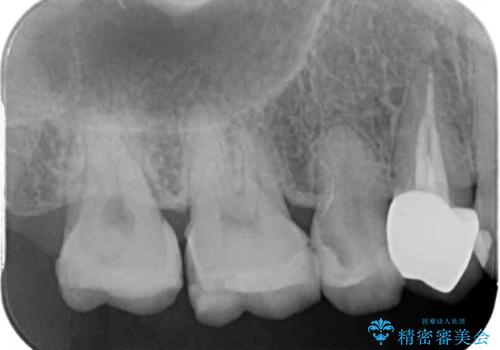

- 奥歯の詰め物や周辺の歯が欠けてしまったとのことで来院された患者様です。

上顎は、元々の詰め物が小さく、欠けた範囲も大きくなかったため、セラミックインレーにて修復治療を行うこととしました。

一方下顎は、元々のむし歯の範囲が広かったため、長期的な予後を踏まえ、セラミッククラウンにて補綴治療を行うこととしました。

特に痛みはありませんでしたが、未然にしっかりとした処置を行うことで、今後むし歯の進行により神経組織が壊死するリスクを低減することが可能となります。